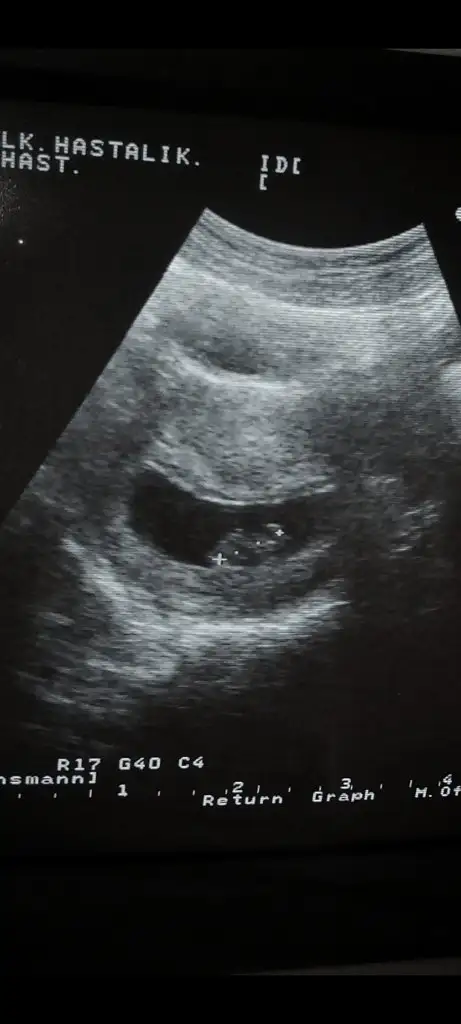

Bakalım hangisi doğru çıkacak sende :)Benim de ilk kese yuvarlakti, 6+5 te de baya solda duruyo bakalim benim de tutucak mi

Sağda ise kız oluyor solda ise erkek oluyor 7. Hafta geçerli değil ilk tutunduğu yer baz alınıyor ve ilk başta sağdaydı diyor bu durumda da ramzi tutmuyor arkadaşımızda sanırımBenimde solda ve yuvarlak değildi o zaman kız mı acaba

Erkek o zaman canımEvet canim ramziye gore de erkekmis demek tutmus benim de boyle solda bakalim ben ne zaman ogtebicem

Ramzi ramziiii benimde ramziye gore kiz eger tutarsa ki oglumda tutmus zamaninda soldaydi oglum .simdiki saga oturmustu . Eger tutarsa herkese benden tatlı hahahaSağda ise kız oluyor solda ise erkek oluyor 7. Hafta geçerli değil ilk tutunduğu yer baz alınıyor ve ilk başta sağdaydı diyor bu durumda da ramzi tutmuyor arkadaşımızda sanırım

Evet sağda kız diyolar o zaman bu teoride çürüdüSağda ise kız oluyor solda ise erkek oluyor 7. Hafta geçerli değil ilk tutunduğu yer baz alınıyor ve ilk başta sağdaydı diyor bu durumda da ramzi tutmuyor arkadaşımızda sanırım